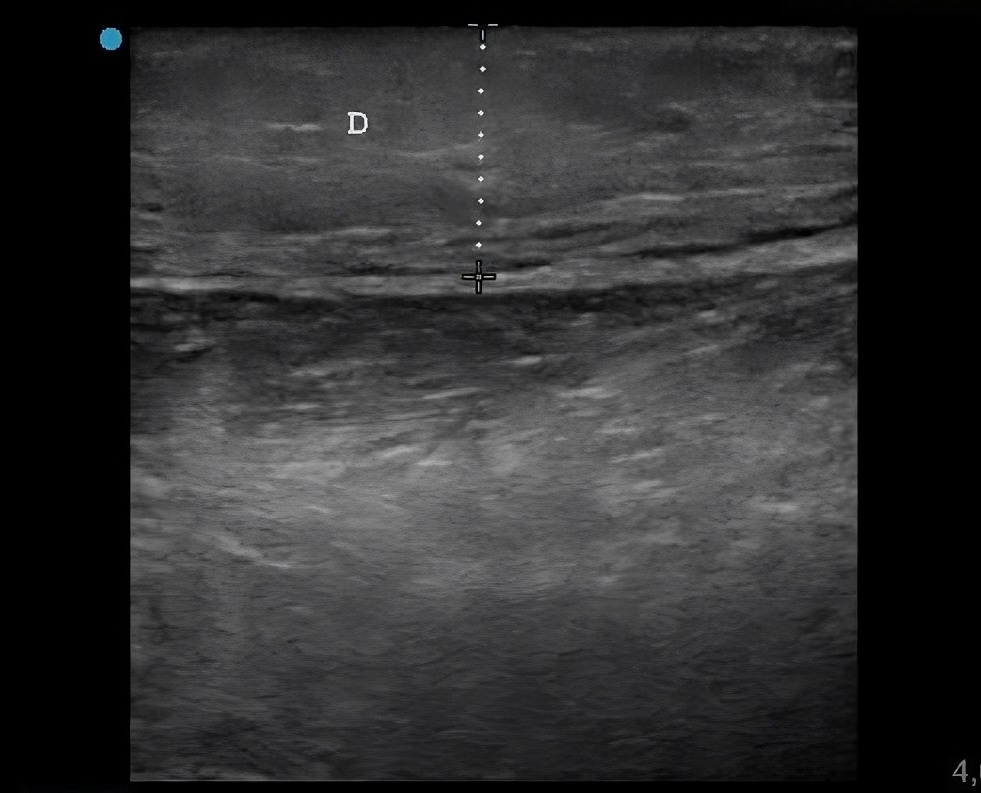

Niño de 7 años que consulta en Urgencias por edema y eritema en la región lateral del tercio distal del miembro inferior derecho tras la picadura de un insecto de 48 horas de evolución. Se encuentra afebril. En la exploración destacan: aumento de temperatura, eritema y edema importante de la piel que rodea la puerta de entrada, que alcanza hasta el dorso del pie derecho, sin limitación a la movilización.